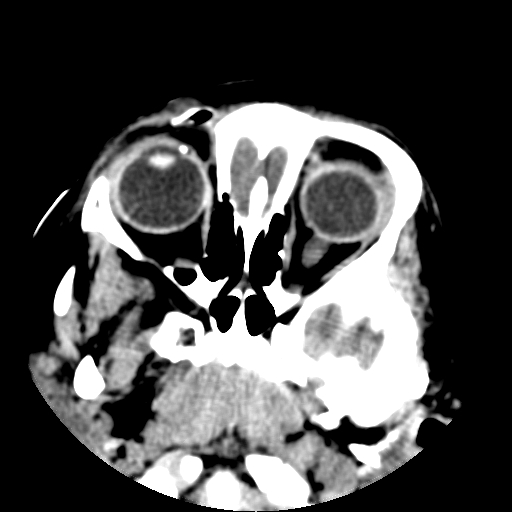

以下是引用深泽交通医院在2009-10-16 8:25:00的发言:[br]右眼环出血伴异物

以下是引用卜一在2009-10-16 15:01:00的发言:[br]右眼球挫裂伤伴异物!

以下是引用拾荒者在2009-10-17 18:38:00的发言:[br]鼻面部皮下积气,右侧睑缘及眼球壁高密度异物影,左侧眼球壁晶状体内侧缘处是圆形低密度影。低密度异物?应提请眼科医生注意。